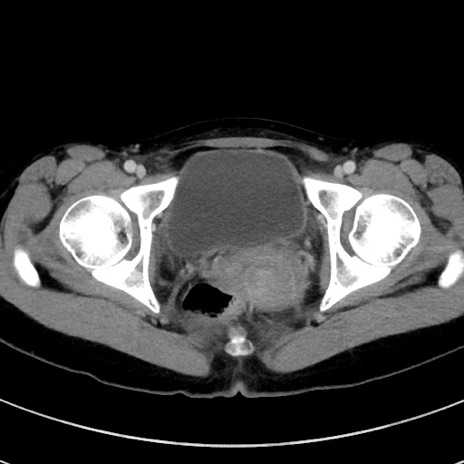

症例17(横断像)

【症例】20歳代女性

【主訴】嘔吐、下腹部痛

【現病歴】昨日夕食後に嘔吐し下腹部痛が出現。本日になっても嘔吐持続し改善しないため来院。

【身体所見】意識清明、BT 37.2℃、BP 108/67mmHg、腹部:平坦、やや硬、下腹部正中から右にかけて圧痛あり、反跳痛軽度あり、tapping pain(+)。

【データ】WBC 13600、CRP 14.94